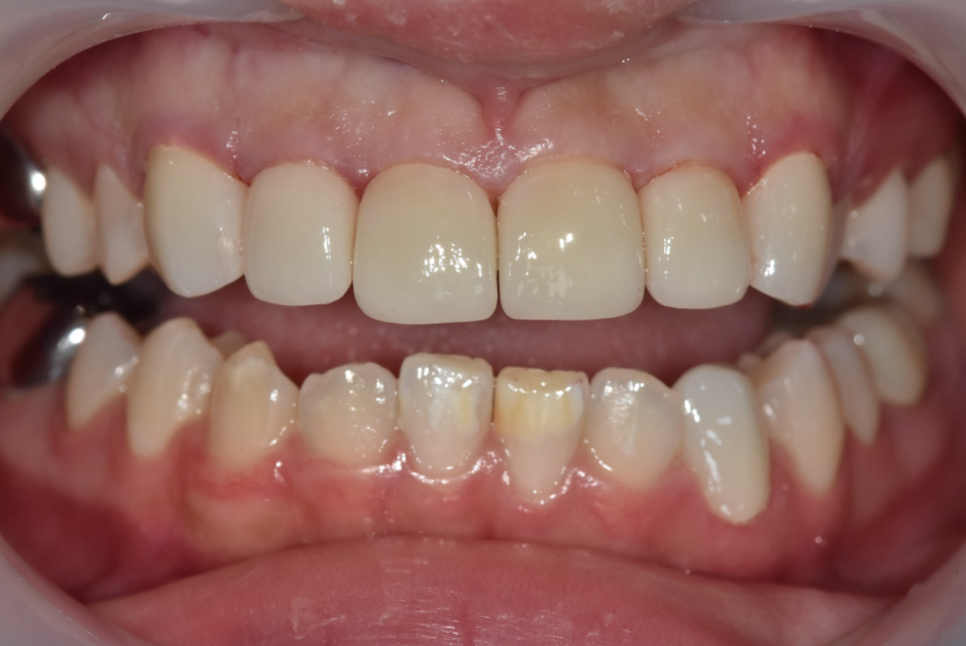

게다가 치아 길이도 전체적으로 가지런하지 않았습니다.

250503 강동구 라미네이트

젊은 여성분이신데 그간 마음고생이 많으셨을 것 같아 안타깝습니다 ㅠㅠ

아래 앞니도 하얀 반점이 여러 군데 있긴 했지만,

특히 왼쪽 아래 송곳니의 반점이 가장 도드라져 보입니다.

그래서 처음엔 위 6개 치아와 왼쪽 송곳니 1개

총 7개의 치아를 라미네이트로 진행할까 했지만,

문제가 있었습니다.